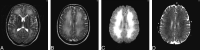

Hypoxic ischemic encephalopathy may cause early deep white matter abnormalities on MR imaging that usually progress to include gray matter and basal ganglia change. Toxic leukoencephalopathy due to heroin inhalation predominantly causes cerebellar and posterior cerebral radiologic change. Both conditions rarely present clinically and radiologically in a delayed manner with subsequent recovery. We report a case of reversible delayed posthypoxic/toxic leukoencephalopathy with no clinical or radiologic evidence of gray matter insult.